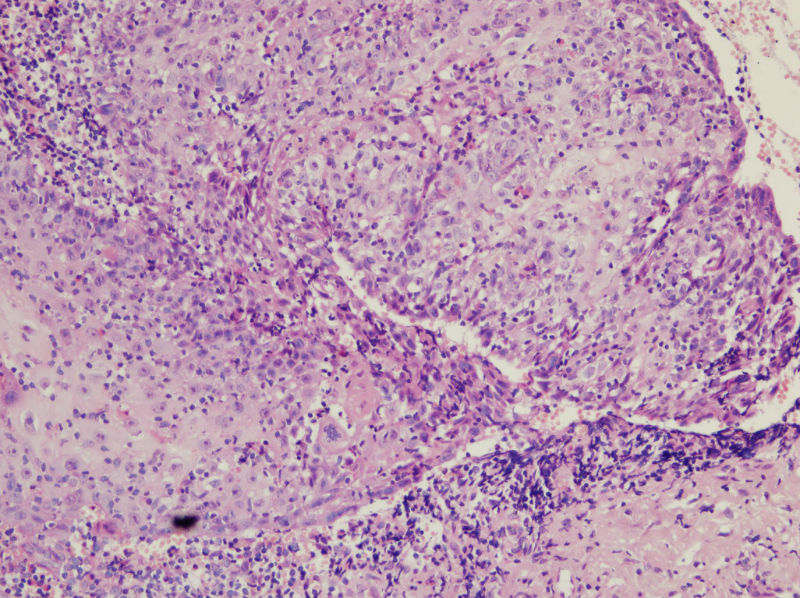

男,45岁,上唇菜花样肿物,请老师指教

图1